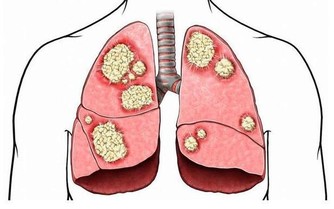

長期積累的結果:腹痛,潰瘍惡化,

皮膚老化,發生癌症的危險性增加。